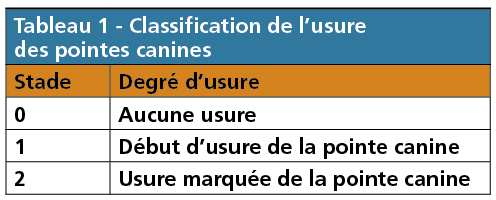

– le degré d’usure des pointes canines maxillaires. Une canine maxillaire ainsi que ses voisines sont photographiées de façon systématisée. L’usure est appréciée selon une adaptation très personnelle que nous faisons de la classification de Broca (1879) citée par Dussarps [12]. Cette classification apprécie l’usure verticale des dents, nous ne l’appliquons qu’aux canines du maxillaire supérieur et n’en retenons que les tout premiers stades qui sont facilement discernables par tout clinicien (tableau 1, fig. 2) ;